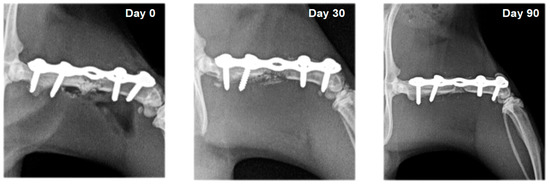

3.2. Radiography